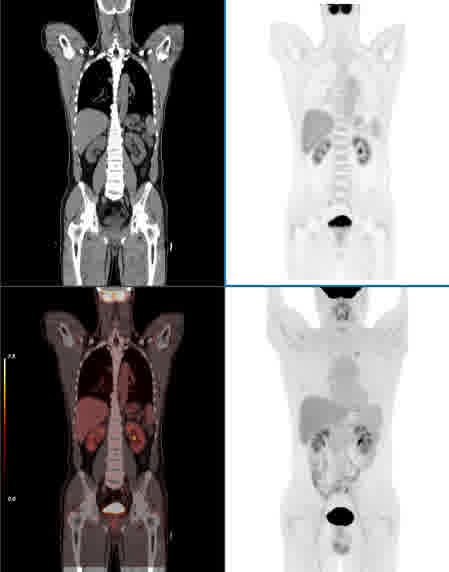

散射校正

CT PET 融合 MIP 无校正 校正后 无校正 校正后 真值图像 传统基于图像的散射校正方法 新型基于能量的散射校正方法 FOV外的高活度射源